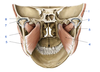

A

Zygomatic process (of temporal bone)

B

Tubercle (of temporal bone)

C

Groove for deep temporal vessels (of temporal bone)

D

Postglenoid tubercle (of temporal bone)

E

Supramastoid crest (of temporal bone)

F

Suprameatal spine (of temporal bone)

G

Opening of external acoustic meatus (of temporal bone)

H

Tympanomastoid fissure (of temporal bone)

I

Mastoid process (of temporal bone)

J

Tympanic part (of temporal bone)

K

Vaginal process (of temporal bone)

L

Styloid process (of temporal bone)

M

Angle (of mandible)

N

Ramus (of mandible)

O

Condylar process (head and neck)(of mandible)

P

Mandibular notch and coronoid process (of mandible)

Q

Anterior (surface of maxilla)

R

Infratemporal (surface of maxilla)

S

Zygomatic bone

T

Zygomatic arch

U

Frontal bone

V

Greater wing of sphenoid

W

Squamous part of temporal bone

1

Articular tubercle